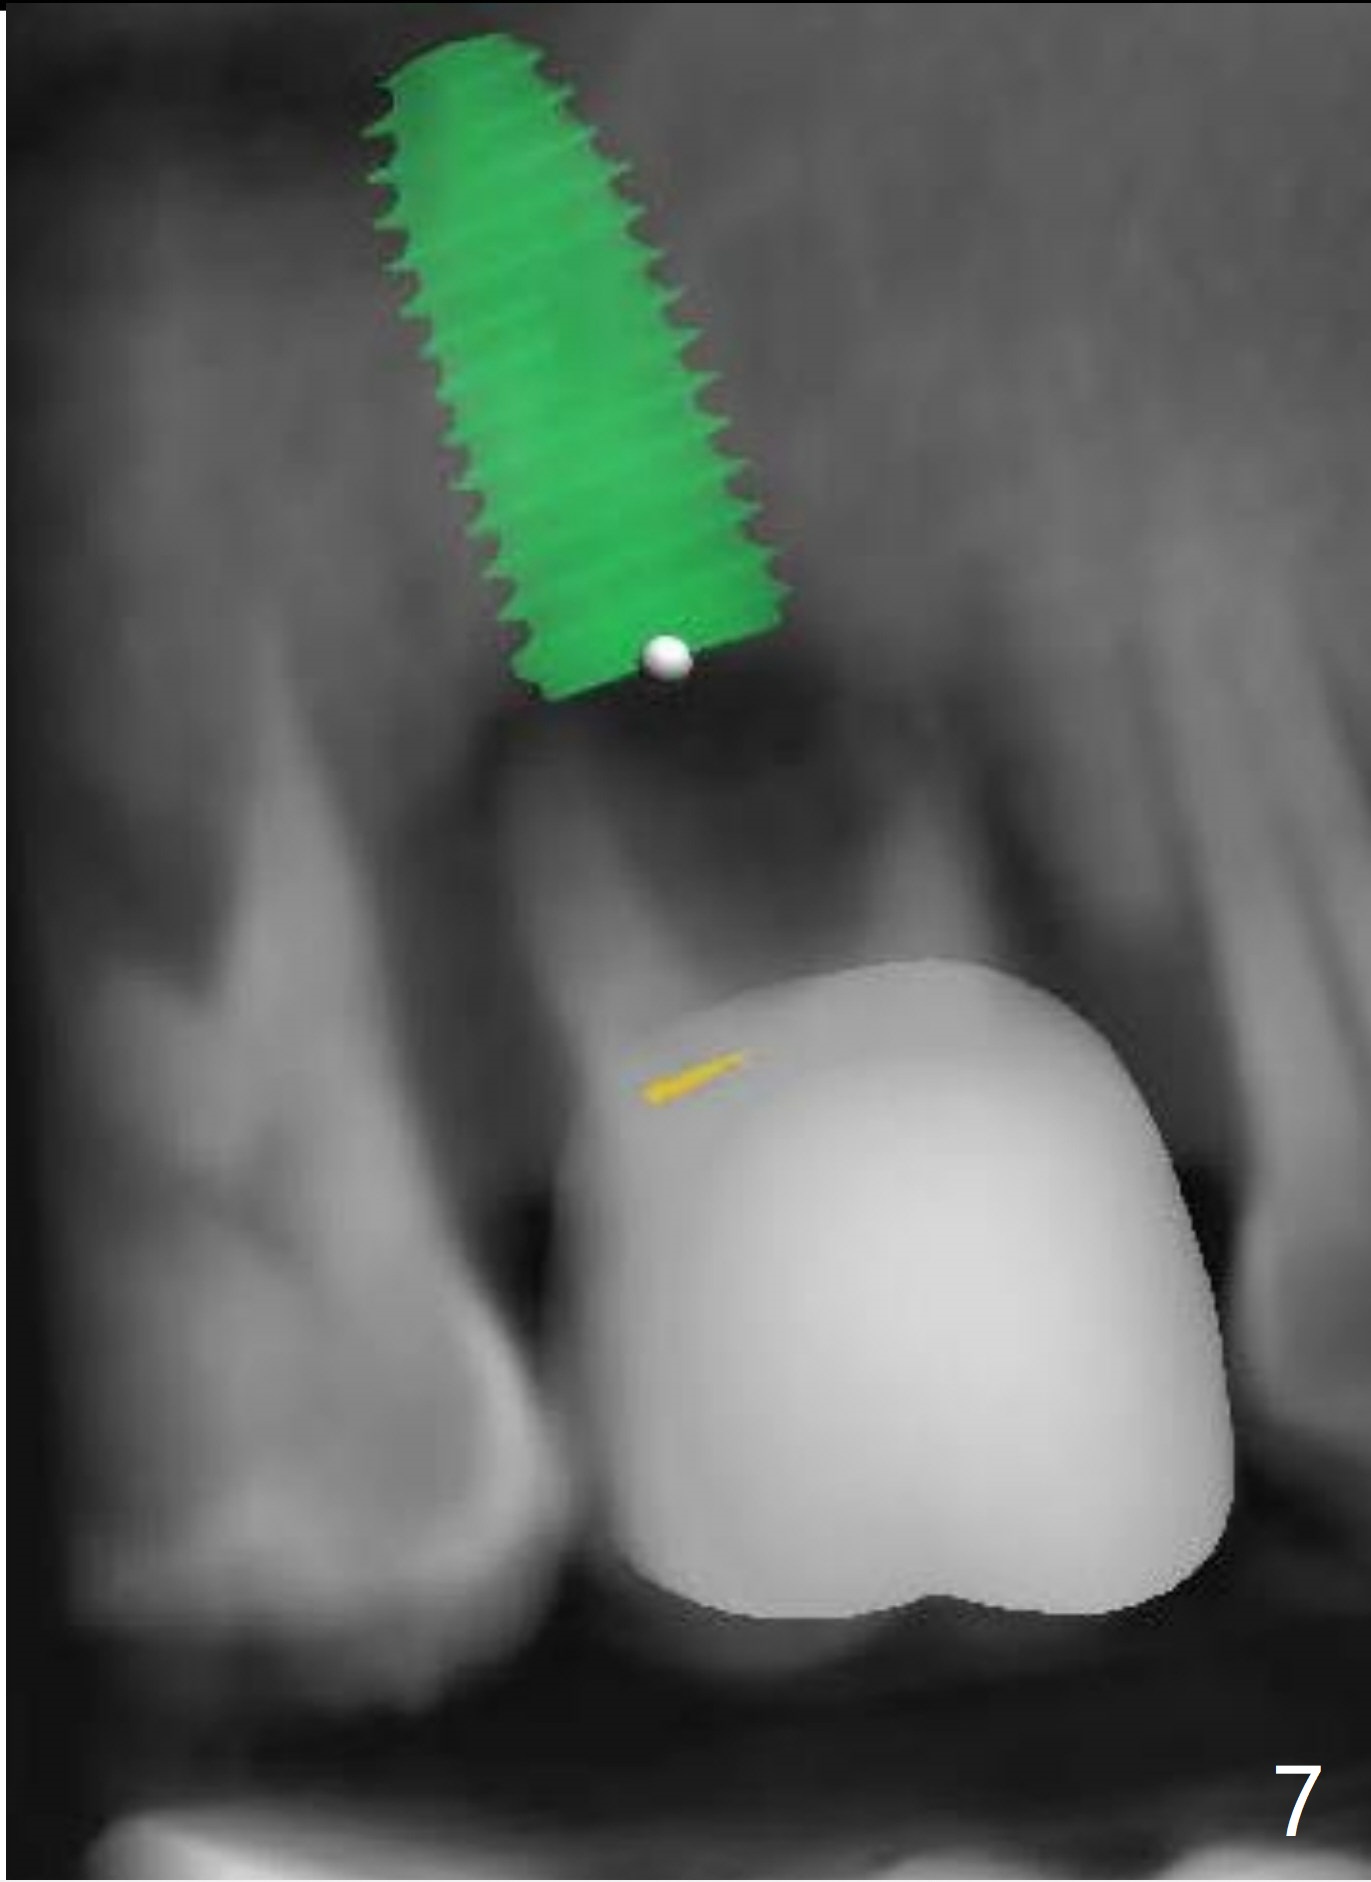

Implant Placement Level and Angulation to Sinus Floor

Return to No Deviation Torque 劈开术